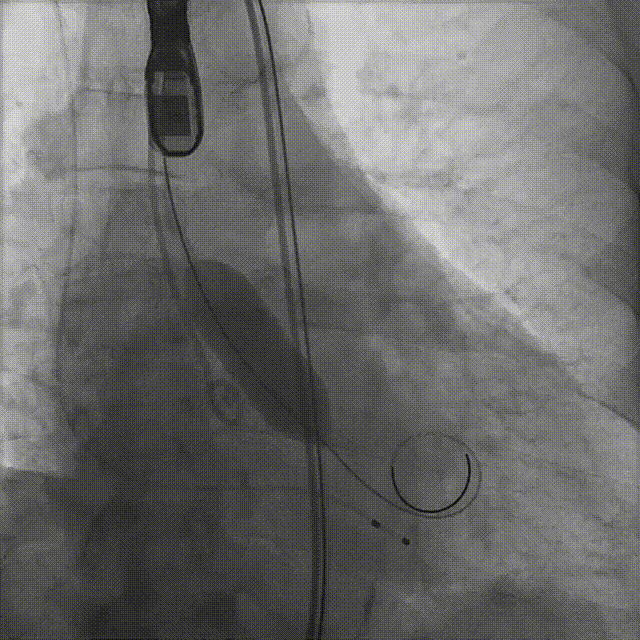

患者病史 男性,74y, 因 “发现心脏瓣膜病 1 年,加重伴喘气半年” 入院。门诊检查显示主动脉瓣重度AS并伴轻-中度AR。患者基础疾病较多:胸腹主动脉多发穿透性溃疡、心功能III级等,手术指征明确,但风险极高。 术前CT LVOT- Annulus 倒梯形,对植入瓣膜有挤压位移风险,Annulus直径23.7mm,瓣叶增厚,钙化集中在无冠窦边缘。 左冠脉开口高度可,瓣叶不长、窦部空间较大,无冠脉风险;室间隔膜部较短,有一定PPI风险,心脏角度37.9°;心室较小,有一定循环崩溃风险,术前注意补液。 术前造影角度及入路:血管入路散在钙化、无迂曲;主动脉弓条件好、双侧股动脉直径大、右股穿刺点侧壁存在环形钙化 左右重合位:RAO 7° CAU 21° 右窦中心位:LAO2 1° CAU 1° 手术策略 20mm球囊预扩后植入AV26瓣膜,同时做好预防循环崩溃、传导阻滞的应急预案。 术中挑战 1)球囊预扩:20mm球囊预扩时无明显 “腰征”,但存在少量反流,提示瓣膜钙化与解剖结构对扩张的阻力不均 2)首次释放偏差:第一次定位释放时,瓣膜在 “开花” 过程中下滑约 3mm,工作位观察显示小弯侧瓣周漏较多(深度超过完全覆膜区),需二次调整。 3)二次精准定位:以猪尾导管为参照,将定位点调整至 “猪尾 - 2mm” 处,结合真实窦底深度(较深)重新释放,最终瓣膜位置稳定,瓣周漏显著减少。 术后即刻效果: 瓣膜形态良好,跨瓣压差从术前的 67mmHg 降至 6mmHg,且无明显瓣周漏,冠脉开口通畅; Commisural Alignment 术后即刻超声: Prostyle A®预装干瓣——助力临床最优化解决方案: √ 平衡的径向支撑力:特殊的解剖结构下位置形态良好,术后跨瓣压差大幅降低,血流动力学改善明显; √ 80%可回收设计:支持术中二次调整释放位置,保证精准释放; √ 平衡的收腰设计&Commissural Alignment设计: 为患者后期冠脉PCI保留了生命通道;